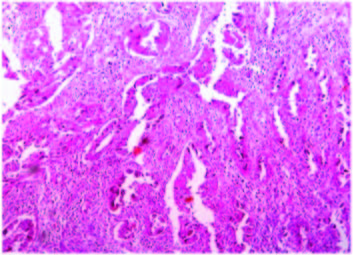

Microscopy shows cords of glandular epithelium infiltrating into myometrium (H&E 100x)

Higher magnification showing clear cells and glandular epithelium (H&E 400x)